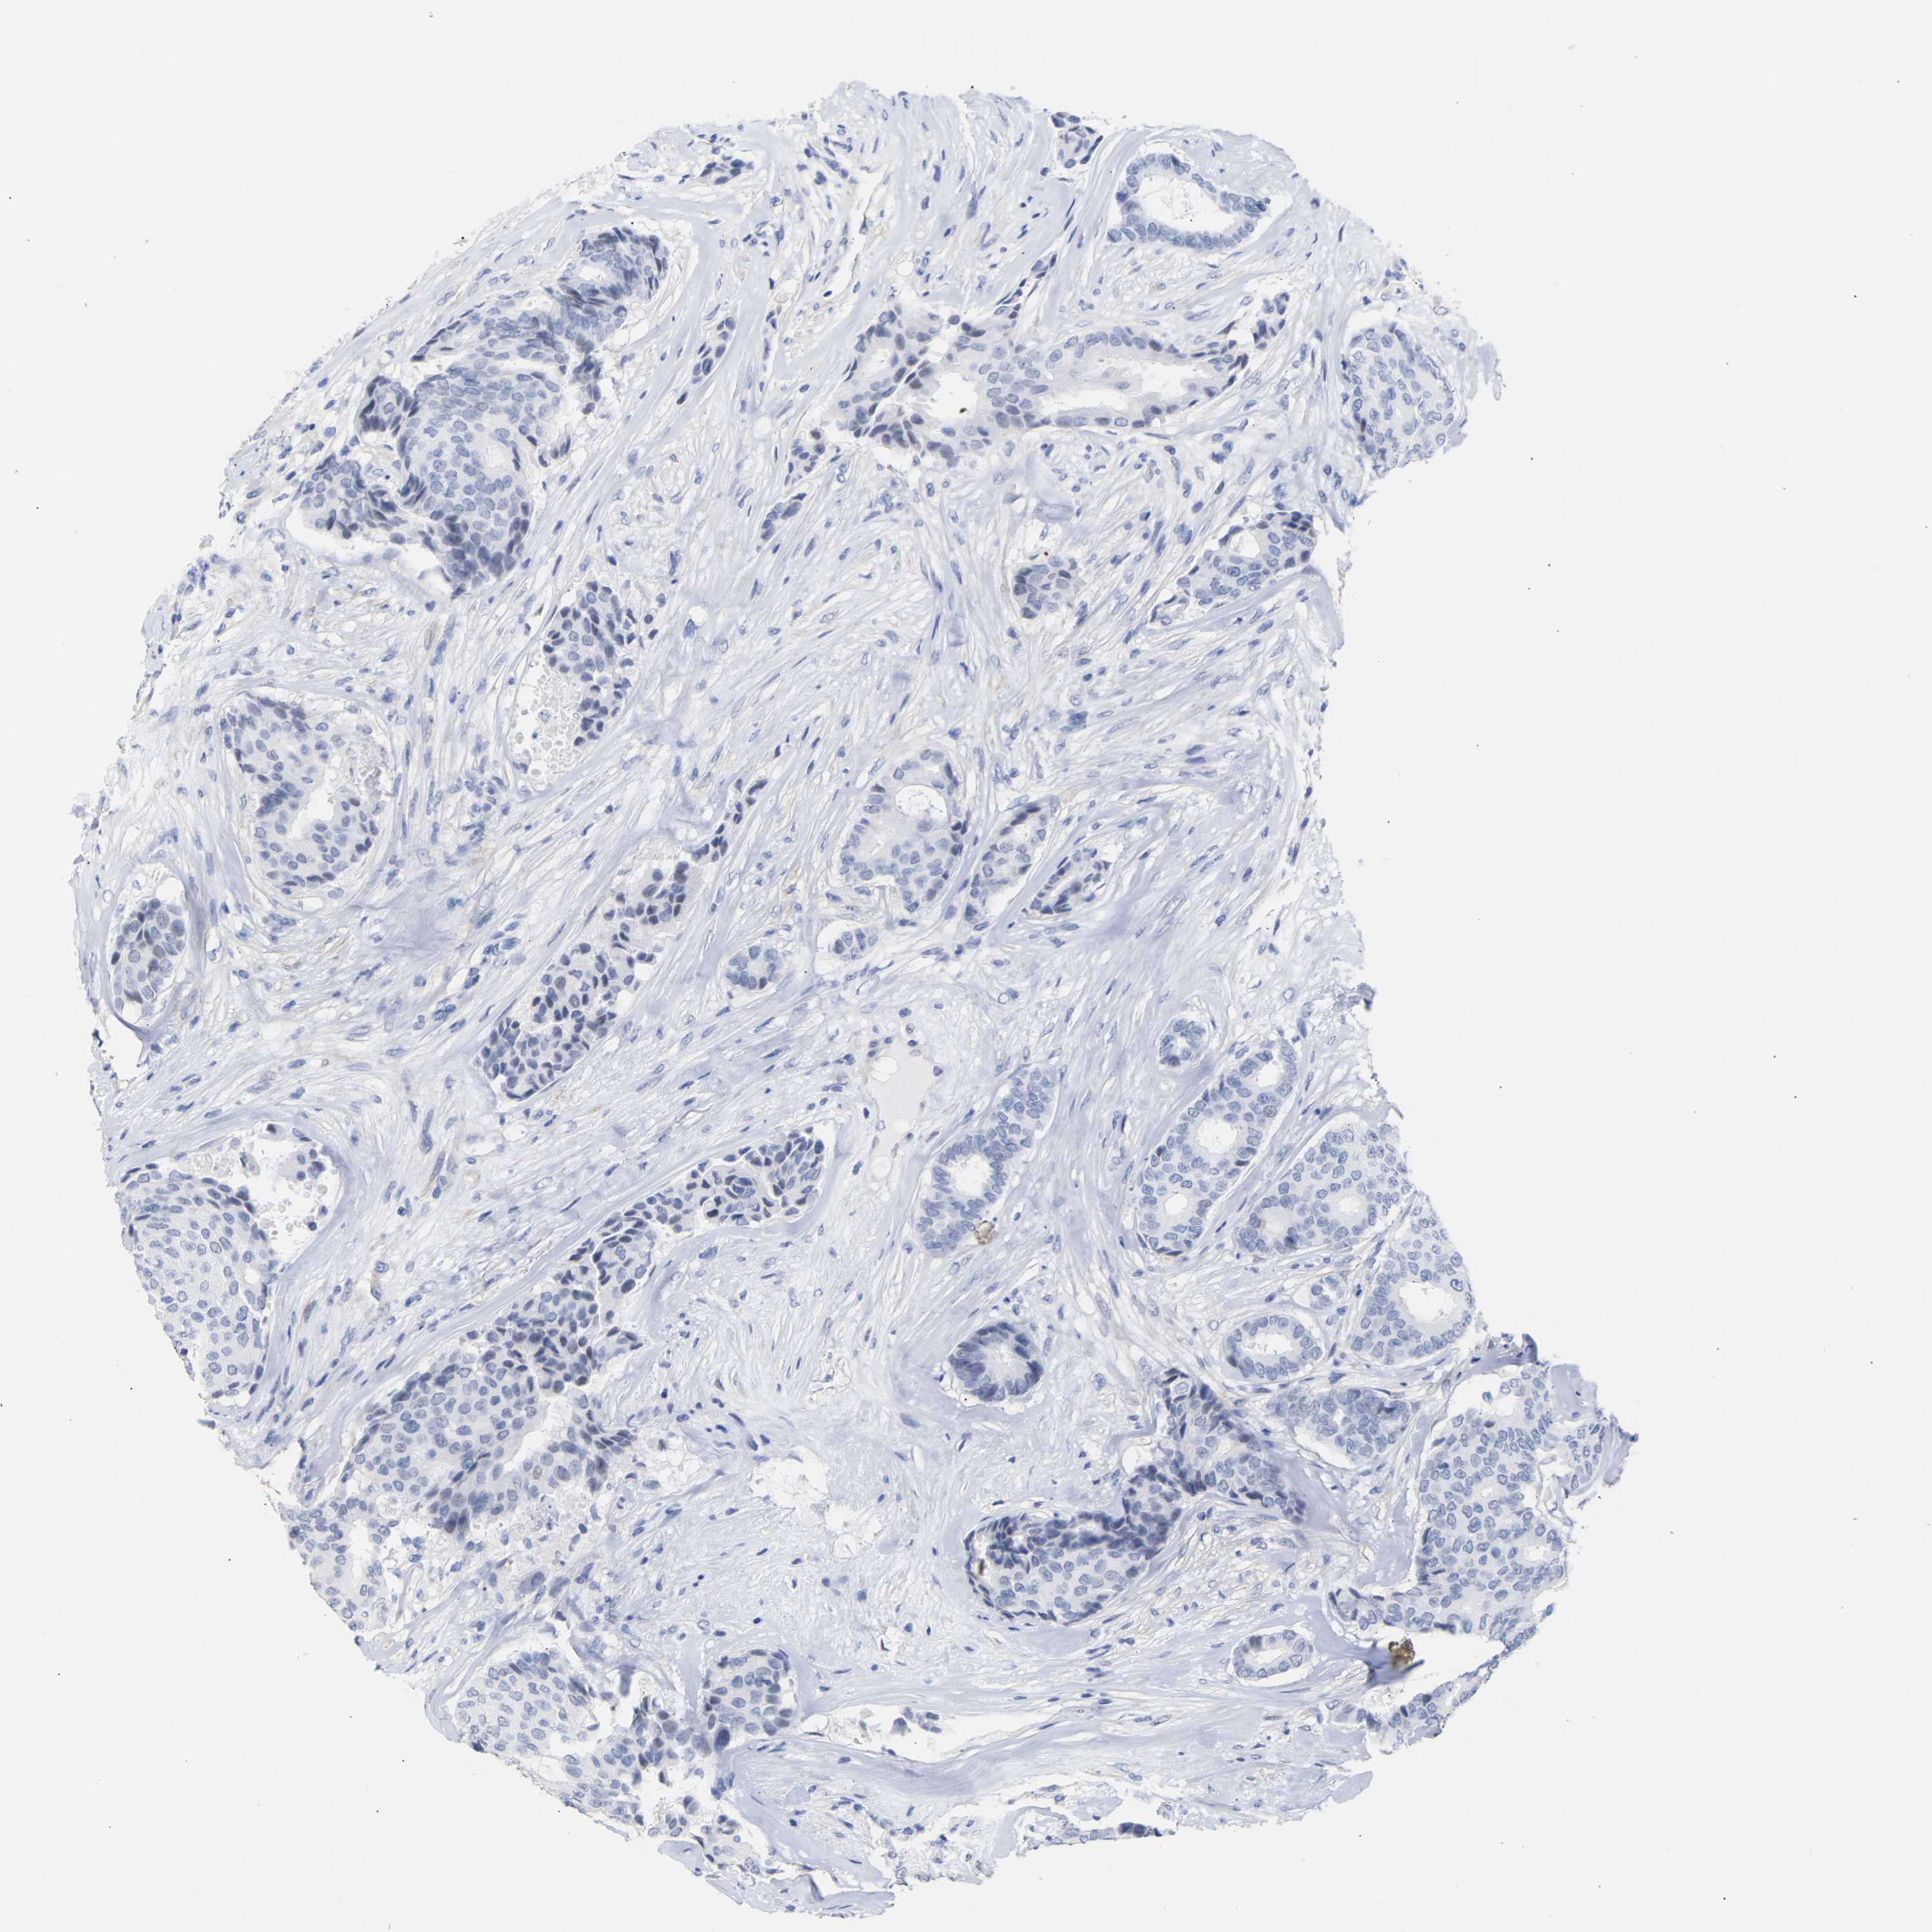

CANCER BREAST CANCER Show tissue menu

BRCA TCGA BRCA VALIDATION PROTEIN EXPRESSION